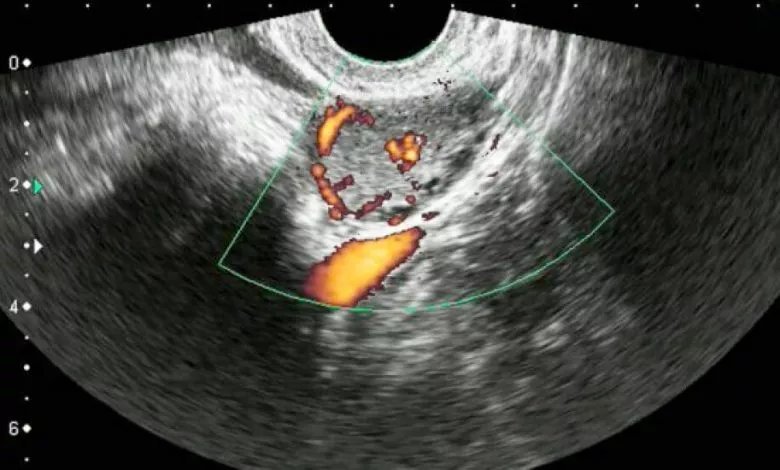

Read More »Кожного місяця жіноче тіло тихо готується до можливого дива — нового життя. І в цій дивовижній подорожі є непомітний, але…